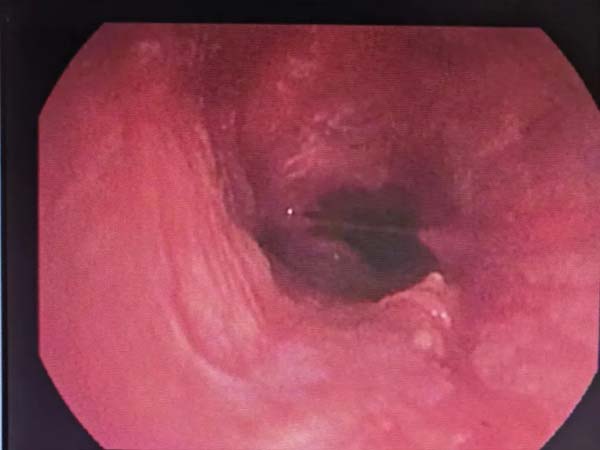

闭锁的气道打开

虽然气道打开了,但是由于肉芽增殖严重,气道反复被坏死物堵塞,因此,又给予低温等离子射频消融肉芽,使气道明显增宽,从原来的完全闭锁,变成狭窄20%。